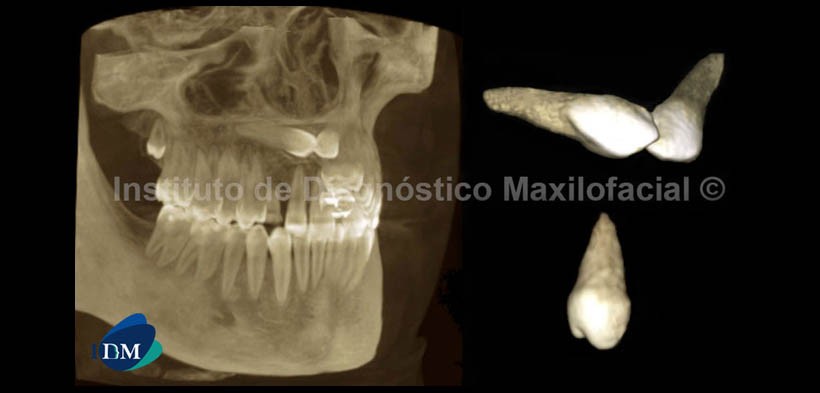

El estudio con tomografía volumétrica muestra en la reconstrucción panorámica( Fig. 1) la presencia de las piezas 1.3 y 2.3, las mismas que se encuentran impactadas entre sí.

Por otro lado, se evidencia la persistencia de las piezas 5.3 y 6.3; además de la alteración del tamaño en la pieza 1.8, compatible con microdoncia.

En las imagenes tridimensionales (Fig. 5 y Fig. 6) se observan las piezas en mención libres de tejido óseo, así como el aislamiento de la pieza 1.8 y la mencionada alteración de tamaño. En la vista axial 3D, se muestra la convergencia de las piezas en sentido póstero anterior y el contacto entre si a nivel coronal.